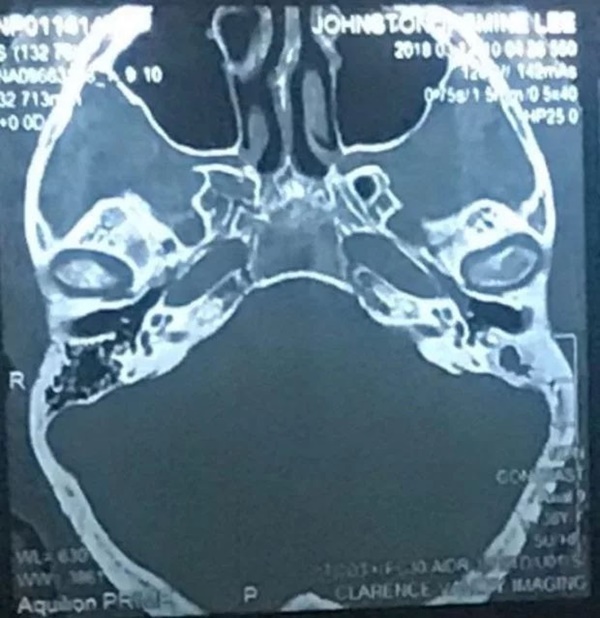

Jasmine Small, 38 tuổi, sống tại Úc, cho biết: Trong nhiều tháng, cô không thể nghe được gì từ bên tai trái. Cô cũng bị đau mỗi khi ngoáy tai và thường thấy tai bị chảy dịch màu nâu, có mùi hôi, thậm chí có lần lẫn cả máu. Khi đi khám, bác sĩ chỉ định cho cô uống thuốc kháng sinh, nhưng do không hiệu quả nên cuối cùng cô được chuyển đến gặp chuyên gia tai mũi họng để tiến hành chụp CT.

Tại đây, bác sĩ đã phát hiện ra bệnh nhiễm trùng sâu bên trong tai cô, đáng lo ngại hơn, ổ nhiễm trùng này còn cực kì gần với não và nguyên nhân gây ra nó là do một sợi bông mỏng rơi ra từ bông ngoái tai. Sau đó, cô Jasmine phải trải qua một cuộc phẫu thuật ngay lập tức với lời cảnh báo của bác sĩ: Nếu để thêm nữa thì có thể sẽ dẫn đến tử vong. Các bác sĩ tin rằng, sợi bông đã "trú ngụ" ở đó tới 5 năm.